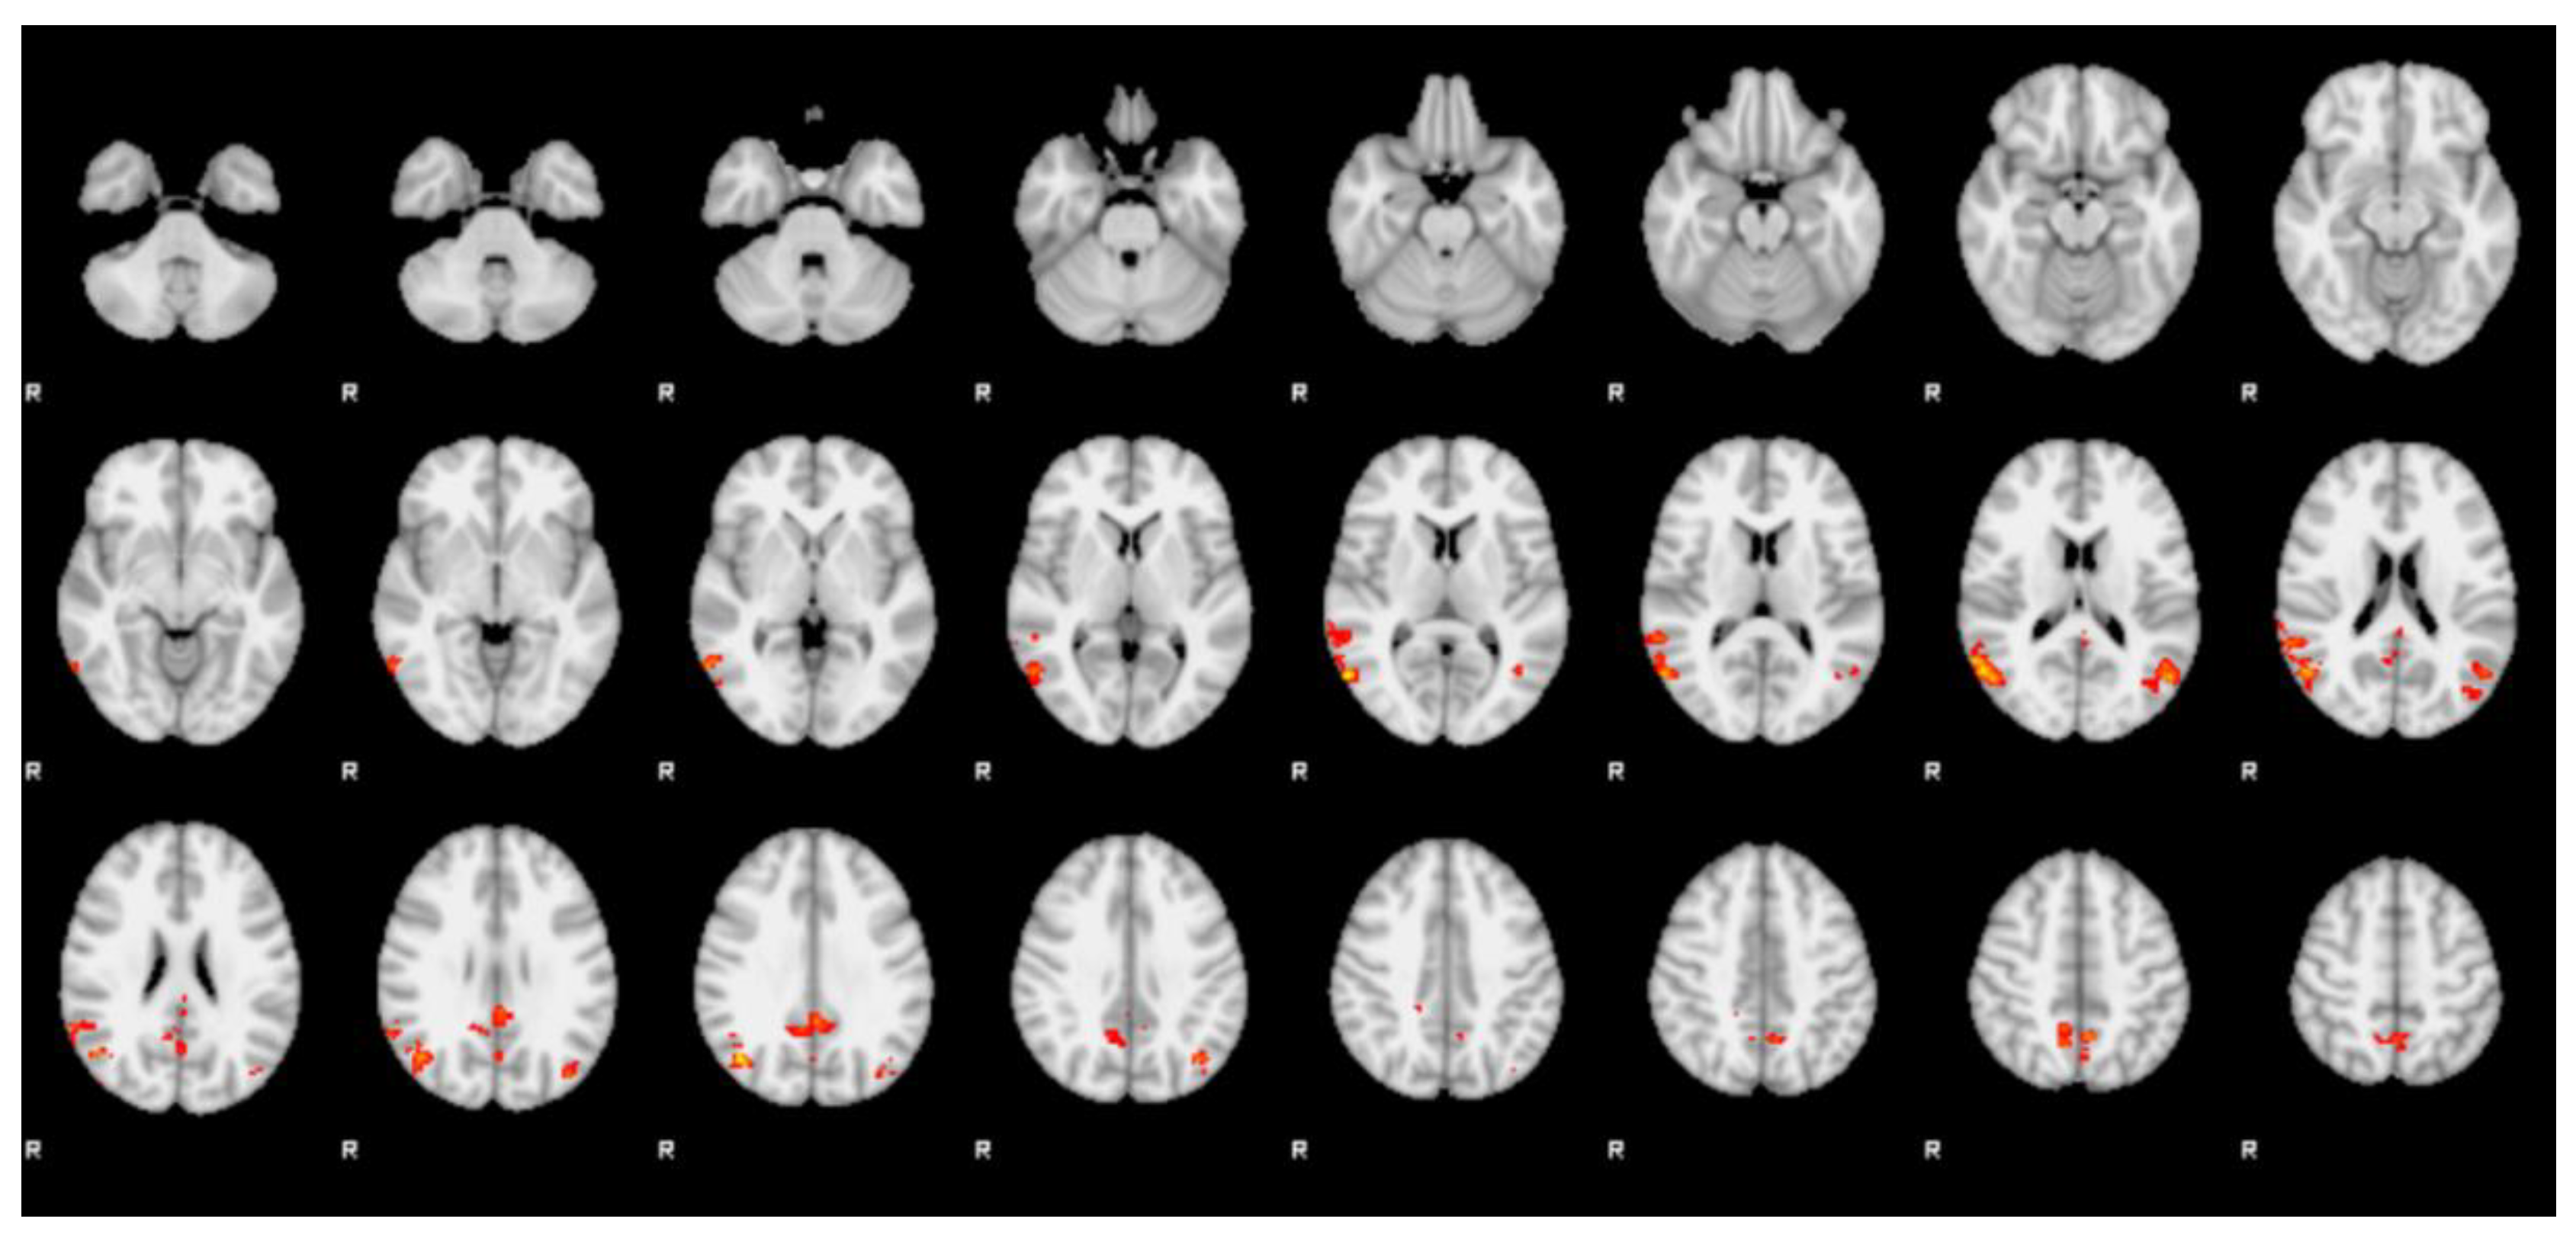

| Cluster | Z-stat | x (mm) | y (mm) | z (mm) | Region (Harvard) |

|---|---|---|---|---|---|

| 1 | 3.99 | 58 | −66 | 8 | right lateral occipital cortex |

| 3.9 | 44 | −68 | 30 | right lateral occipital cortex | |

| 3.71 | 56 | −62 | 16 | right lateral occipital cortex | |

| 3.64 | 60 | −56 | 16 | right angular gyrus | |

| 3.56 | 48 | −64 | 22 | right lateral occipital cortex | |

| 3.52 | 50 | −68 | 16 | right lateral occipital cortex | |

| 2 | 3.44 | −2 | −46 | 30 | left cingulate gyrus, posterior division |

| 3.06 | −2 | −40 | 28 | left cingulate gyrus, posterior division | |

| 2.83 | 6 | −52 | 32 | right cingulate gyrus, posterior division | |

| 2.82 | 12 | −54 | 34 | right precuneus cortex | |

| 2.78 | 0 | −66 | 26 | left precuneus cortex | |

| 2.75 | 8 | −56 | 24 | right precuneus cortex | |

| 3 | 3.58 | −52 | −66 | 16 | left lateral occipital cortex |

| 3.14 | −40 | −68 | 36 | left lateral occipital cortex | |

| 3.06 | −48 | −58 | 16 | left angular gyrus | |

| 3.02 | −38 | −76 | 30 | left lateral occipital cortex | |

| 2.84 | −42 | −64 | 10 | left lateral occipital cortex (l-OFA) | |

| 2.8 | −40 | −72 | 18 | left lateral occipital cortex (l-OFA) | |

| 4 | 3.38 | −2 | −56 | 50 | left precuneus cortex |

| 3.09 | 10 | −58 | 46 | right precuneus cortex | |

| 3.06 | 10 | −50 | 48 | right precuneus cortex | |

| 3.01 | 12 | −58 | 50 | right precuneus cortex | |

| 2.74 | −12 | −62 | 60 | left lateral occipital cortex | |

| 2.72 | −10 | −68 | 58 | left lateral occipital cortex |